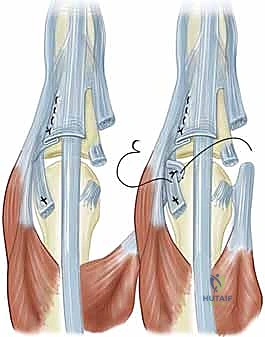

- وتر الباسطة الرقمية المشتركة (Extensor Digitorum Communis - EDC): هو اللاعب المركزي والنجم في إجراء اليوم الجراحي. يتم الاحتفاظ بهذا الوتر في المنتصف تماماً فوق قمة مفصل MCP بواسطة هياكل تُعرف بـ الأربطة السهمية (Sagittal Bands).

- الأربطة السهمية: هي ألياف مستعرضة قوية تنشأ من غطاء الباسطة (Extensor Hood) وتتصل من الناحية الراحية بالصفيحة الراحية والرباط بين الأمشاط المستعرض، لتشكل آلية تشبه "الحبال" أو "المقلاع" (Sling mechanism) تحافظ على الوتر في مكانه. يُعتبر الرباط السهمي الزندي عموماً أقوى وأكثر كثافة من نظيره الكعبري، وهو عامل بيوميكانيكي يساهم في سهولة انزلاق الوتر نحو الجهة الزندية (Ulnar Subluxation) عندما يضعف الرباط الكعبري بسبب المرض.

- تمزق الرباط السهمي الكعبري (Radial Sagittal Band Attenuation): التورم المستمر يضغط على الأربطة السهمية التي تثبت الوتر الباسط. نظراً لأن الرباط الكعبري أضعف بطبيعته، فإنه يتمدد أو يتمزق أولاً.

- الانزلاق الزندي للوتر الباسط (Ulnar Subluxation of EDC): بمجرد ضعف الرباط السهمي الكعبري، ينزلق وتر الباسطة (EDC) من أعلى قمة المفصل نحو الوادي الزندي بين الأمشاط. عندما يحدث هذا، يفقد الوتر قدرته على بسط الإصبع بفعالية، وبدلاً من ذلك، تصبح قوة سحبه مساهمة في زيادة الانحراف الزندي للأصابع.

- تقلص العضلات الداخلية (Intrinsic Tightness): مع استمرار التشوه، تتقلص العضلات بين العظام الزندية، مما يثبت التشوه ويجعله غير قابل للتصحيح السلبي (Fixed Deformity).